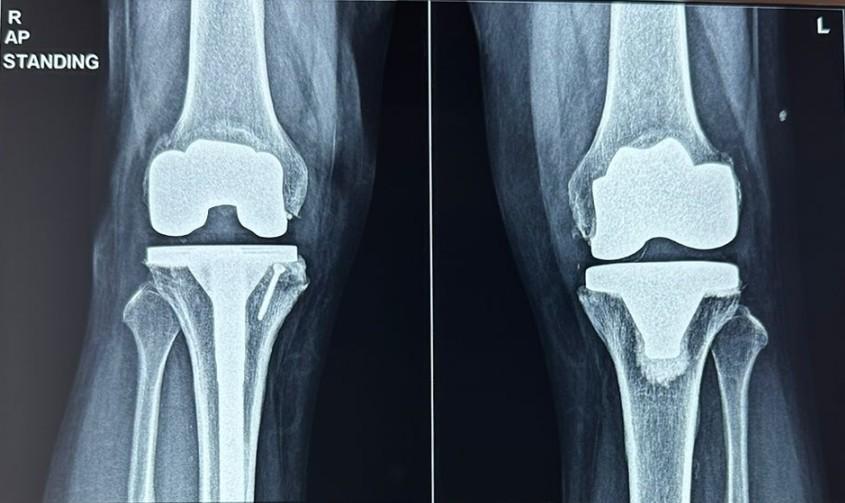

🌟 Transform Your Life with Total Knee Replaceme...

Best Knee Replacement Surgeon in andheri Vile P...

Best Orthopaedic Surgeon In Vile Parle Best Or...